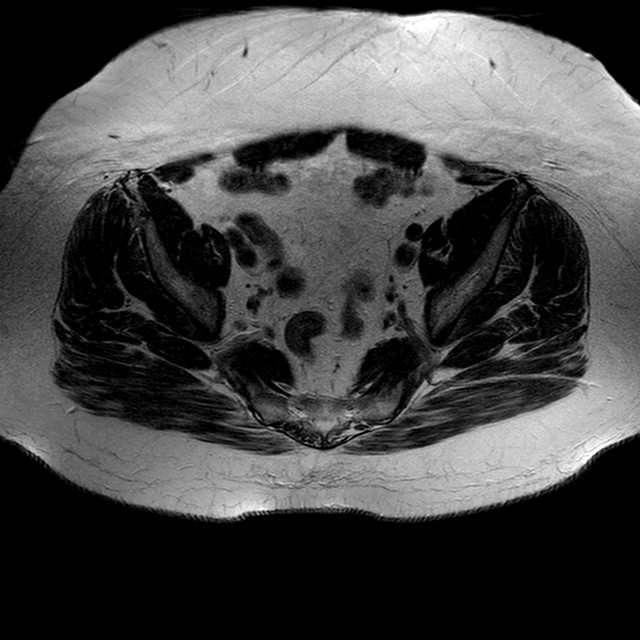

Esami: RMN BACINO

T2w TSE

Evidenti e simmetriche alterazioni osteofitosiche in regione coxo femorale con riduzione delle rime articolari. Degenerazione completa del cercine glenoideo. Non attuali segni di versamento articolare. Non segni di edema osseo che escludono attuale algodistrofia od osteonecrosi. Lieve e simmetrica riduzione del trofismo della muscolatura glutea.